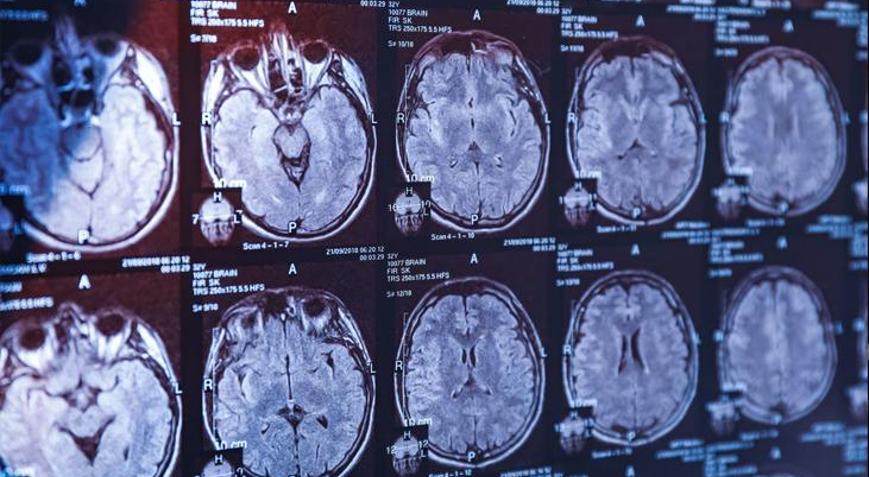

Parkinson, sinir hücrelerinin zamanla kaybolduğu ilerleyici bir nörolojik durum olarak biliniyor. Bu durum, hareketi kontrol etmede önemli bir rol oynayan dopamin kimyasalının azalmasına yol açar.